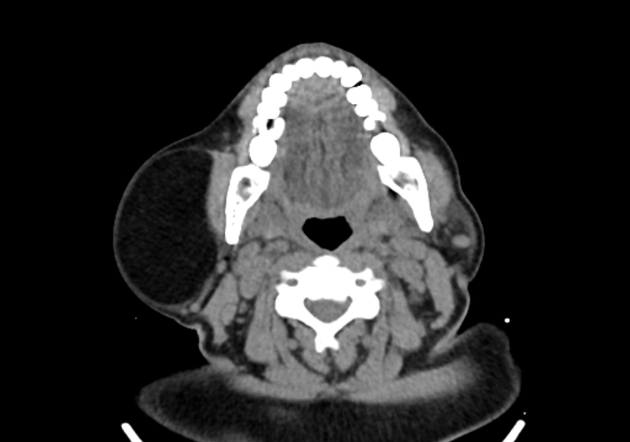

Ларингоцеле на КТ: визуализация и диагностика